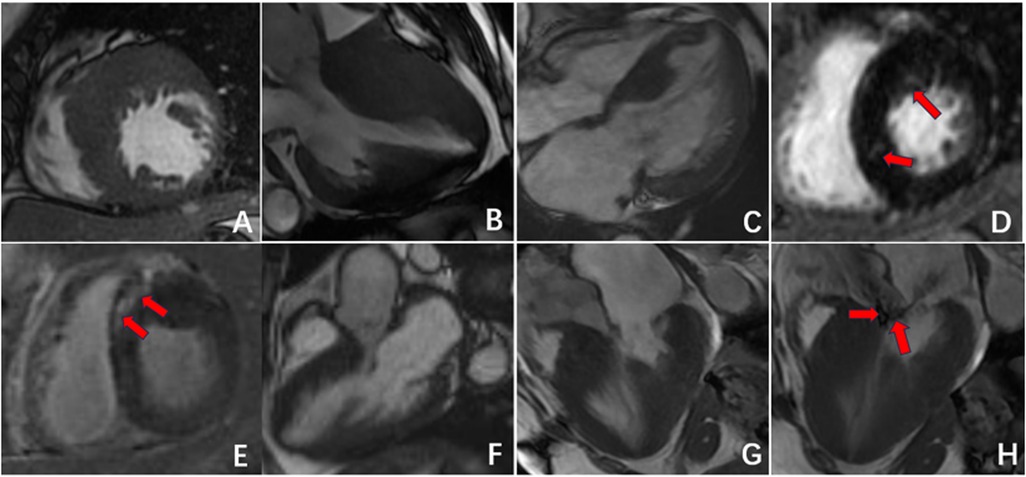

Figure 3

Radiographic findings of HCM. (A–C) Asymmetric myocardial hypertrophy; (D,E) mid-myocardial enhancement (red arrow); (F–H) HCM resulting in signs of an outflow tract with a systolic high-velocity blood flow signal (red arrow).

Both CA and HCM can present with left ventricular myocardial hypertrophy and increased mass, but their underlying pathophysiology and imaging features are distinct. CA occurs primarily due to diffuse deposition of amyloid substances in the left ventricle, leading to symmetrical and uniform thickening of the myocardium (14). In contrast, HCM is characterized predominantly by asymmetrical hypertrophy of the left ventricular myocardium, especially hypertrophy of the interventricular septum myocardial cells and fibrosis in the hypertrophic myocardial area (15–17), sometimes resulting in signs of outflow tract narrowing and obstruction (18). Additionally, CA patients often have pleural effusion or pericardial effusion, which may be related to heart failure or amyloid substance deposition (19). These overlapping clinical manifestations contribute to a high rate of misdiagnosis, underscoring the value of advanced imaging techniques for differentiation.

The results of this study indicate that delayed enhancement CMR patterns can serve as a useful method for distinguishing between CA and HCM. The enhancement pattern of CA is characterized mainly by subendocardial diffuse enhancement and transmural enhancement, findings that have been widely described in previous studies of cardiac amyloidosis using late gadolinium enhancement (20, 21). This enhancement pattern may be related to the deposition pattern of amyloid substances, which initially deposit subendocardially with blood flow distribution and progressively involve the entire myocardium, manifesting as transmural enhancement as the disease progresses. Additionally, when amyloid substances are deposited in other cardiac chambers, they can manifest as enhancement of varying degrees in the left atrium, right ventricle, and right atrium. Some researchers have proposed that the delayed enhancement imaging features of CA are related to the deposition of amyloid substances and thus correspond to CA prognosis (22–24). In contrast, delayed enhancement in HCM presents mainly as patchy enhancement in areas of hypertrophic myocardium, especially in the middle layer of the interventricular septum. In patients with CA, a distinctive phenomenon, termed the “chaotic sign”, is frequently observed on delayed enhancement images. We define this sign as a loss of normal contrast between the blood pool and myocardium, producing a diffusely hypointense ventricular cavity with blurred endocardial borders. This appearance reflects markedly altered gadolinium kinetics due to diffuse amyloid infiltration and rapid clearance of contrast from the blood pool. Similar “dark-blood” or “non-nullable myocardium” findings have been described in previous studies of cardiac amyloidosis (25, 26). Left ventricular systolic and diastolic deformation is achieved through the combined action of the three layers of myocardial fibers: subendocardial myocardium, mid-myocardium, and subepicardial myocardium. Each layer of myocardial fibers affects strain in different directions according to the angle of orientation (27, 28). The subendocardial myocardium, which is parallel to the long axis of the heart, affects mainly longitudinal strain, whereas the mid-myocardial fibers, oblique to the heart's outer surface, affect mainly circumferential strain; radial strain is affected by the combined action of all myocardial layers (29). In CA patients, amyloid proteins are deposited in the subendocardial myocardium in the early stages of the disease, predominantly affecting longitudinal strain. Therefore, the decreased longitudinal strain of the left ventricle is the most sensitive indicator for evaluating myocardial amyloidosis (30, 31). The results of this study indicate that, compared with the HCM and control groups, the CA group exhibited significantly reduced GLS, suggesting more pronounced damage to the subendocardial longitudinal myocardium in CA patients. Additionally, the GRS and GCS values in CA patients were significantly lower than those in the HCM and NC groups. The variation in these parameters may suggest that amyloid substance deposition gradually affects the mid-myocardium and subepicardial myocardium, indicating further deterioration in CA.